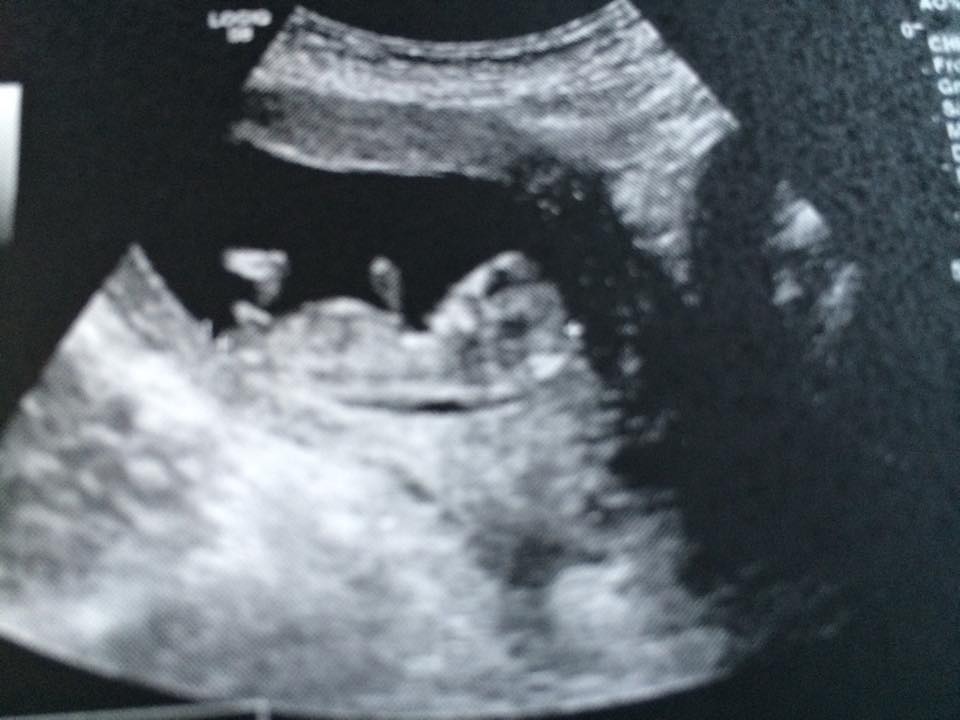

PINK Or BLUE???

Boy!

Boy nub!

Thanks so far ladies! I thought it was a perfect angle against the spine for BLUE TOO But I had to make sure!! :superhero:

Ladies, I apologize that I have not been here in months and totally forgot that I posted this. But it's a REALLY great nub shot, one to which I was 100% percent on right when I saw it. But anyway, it was confirmed a beautiful little

BOY